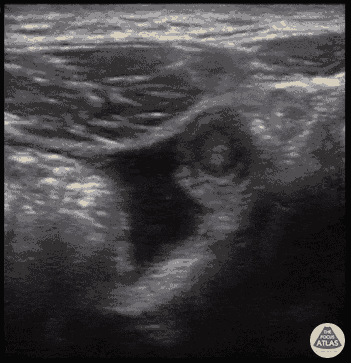

18 y/o with severe acute onset RLQ abdominal pain, associated with vomiting. Temp 100.8 with guarding over RLQ. POCUS performed and revealed appendicitis. 8mm dilated, non-compressible, aperistaltic appendix with an appendicolith present (hyperechoic structure in blind end of appendix) surrounded by free fluid. Tender directly over the appendix. The psoas muscle can be seen on the right side, and bowel can be seen to the left. Drs. Bryan Jarret, Sathya Subramaniam - Kings County/SUNY Downstate